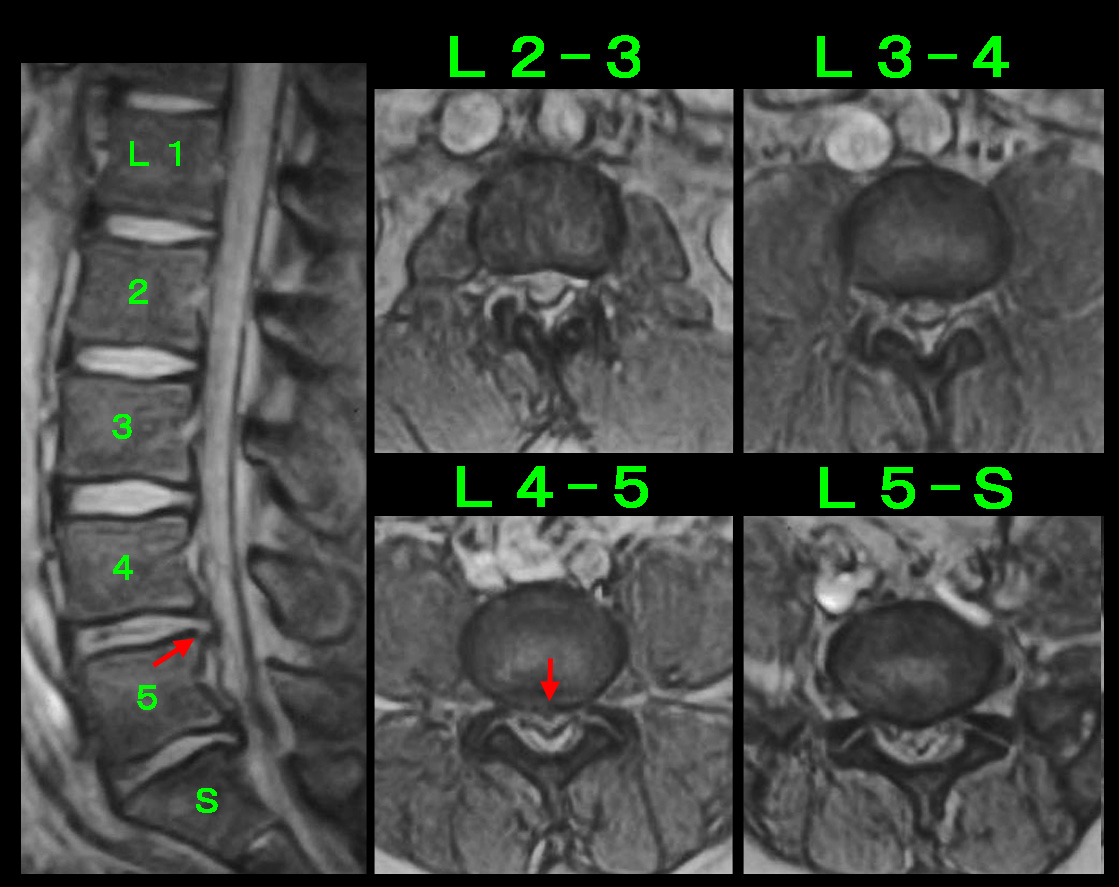

まずは、25年前の患者さんです。35才の男性で建設業の現場監督でプロレスラーのような体型の方でした。平成13年3月23日右臀部痛が発症し、2日後の25日には右腓腹部(ふくらはぎ)の痛みも出て歩行困難となられ、3月26日に当院を受診されました。腰に起因する坐骨神経痛と判断しますが、私の経験では坐骨神経痛は服薬で軽減することはまれです。腰椎MRI検査を行い、腰のどこに(どの高位に)原因があるのかを診断し、そこに神経根ブロックを行うことが最も効果が期待できます。検査を受けずにどこが病因なのかを正確に判断しないでブロックを受けてもあまり効果がえられないということになります。ブロックのパンフレットの①硬膜外ブロックや②仙骨裂孔ブロックはそのようなブロックとなります。この患者さんもMRI検査を行いました。

開業当初のMRIでの画像で今より画質悪いものですが、診断は十分可能です。L4-5とL5-Sに椎間板ヘルニアを認めすが、L4-5の方が脊髄(腰の背中側に長くつながっている領域です)の圧迫は強いと判断し、左L5神経根ブロックを勧めました。しかし患者さんは、以前他の整形外科でブロックを受け、失神しそうなほどの痛みがあったので、絶対いやだと断られました。そこで臀部に局注(ブロックのパンフレットの④トリガーポイント注射となります)を施行し、鎮痛剤を処方しました。